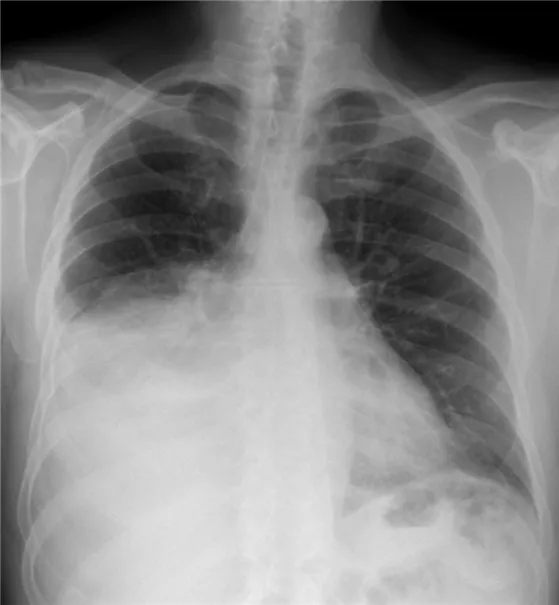

52세 여성이 4일 전부터 시작된 우측 가슴 통증과 발열, 기침 증상으로 내원했다. 환자는 3주 전부터 우측 옆구리에 통증을 느꼈다고 한다. 가슴 X선 검사 결과를 바탕으로 진단하였다. 흉수 검사 결과는 아래와 같다. 이 환자의 치료 방법은 무엇인가?

• 고열, 기침, 가슴 통증이 있는 환자의 가슴 X선에서 우측 폐의 pleural effusion이 확인된다.